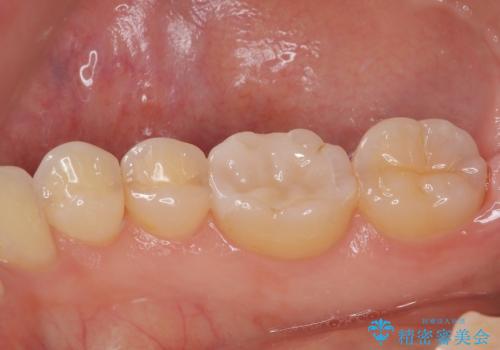

ハイブリッドインレーの装着時には、唾液の侵入を防ぐために、ラバーダム防湿を行いました。

見た目、機能面共に大変喜んでいただきました。